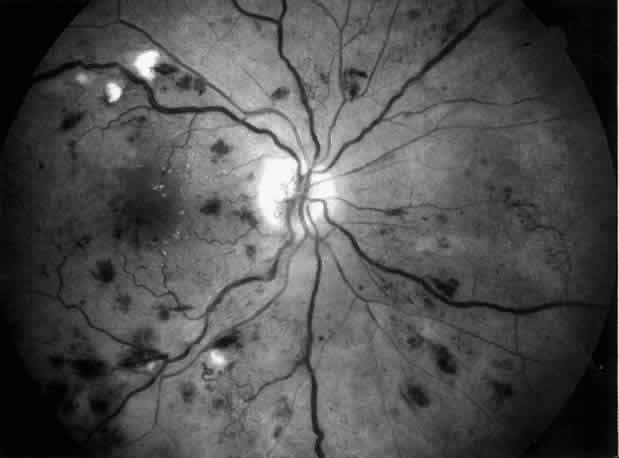

approach in preventing blindness.71  Fig. 5. Combined diabetic and hypertensive retinopathy in a 52-year-old patient

with long-standing diabetes and end-stage renal disease. Note optic disc

and retinal new vessels, diffuse retinal edema, numerous hemorrhages, and

several cotton-wool spots along the main veins. Fig. 5. Combined diabetic and hypertensive retinopathy in a 52-year-old patient

with long-standing diabetes and end-stage renal disease. Note optic disc

and retinal new vessels, diffuse retinal edema, numerous hemorrhages, and

several cotton-wool spots along the main veins.